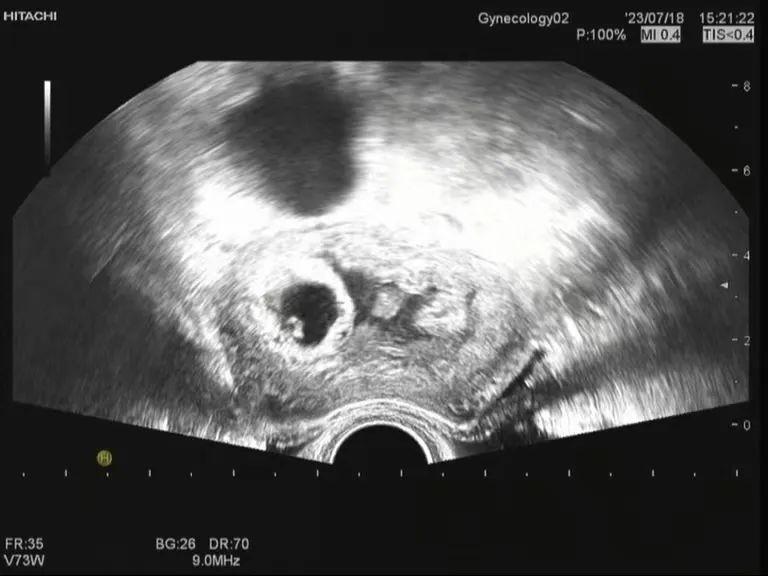

张女士夫妇的求子之路举步维艰,从结婚后开始备孕,辗转多家医院,打听到做试管婴儿需要多次往返奔波、花费庞大,让这对夫妇望而却步,2023年4月攀枝花市妇幼保健院试管婴儿技术获批运行,张女士夫妇第一时间决定在该院生殖医学中心进行试管婴儿,根据张女士的病情,在医师的悉心指导下为其制定了个体化促排方案,于2023年6月16日取卵,6月19日行胚胎移植术(ET),移植过程顺利,7月4日验血HCG值为423.69mIU/L,7月18日B超见孕囊、胎芽及心管搏动!这是攀西地区完成的首例试管婴儿成功妊娠!